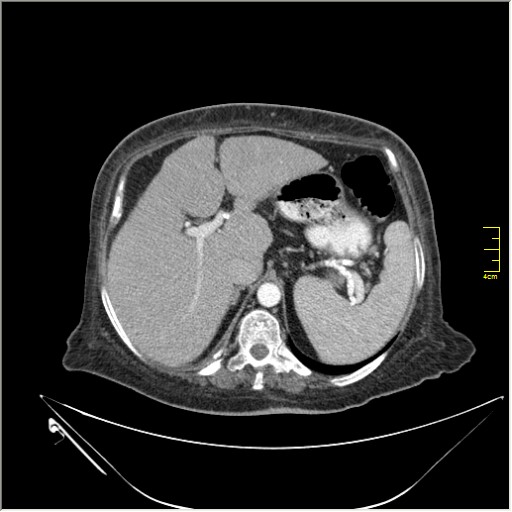

Весьма актуальная тема. Часто при проведении КТ исследования по тому или иному поводу, мы находим патологию, никак не связанную с клиникой пациента и не являющимся причиной обращения в кабинет КТ. Очень важно знать; как с этим быть, какие рекоммендации и действия необходимо предпринять. Для примера приведу одно наблюдение.

N.B. Все "находки" никак не были связаны с клиникой.

образование в правом надпочечнике

Incedentaloma правого надпочечника

Находки 2:

1.Образование правого надпочечника с плотностью жира, липома. Ничего делать не надо. По другим вариантам incidentalomas, Др. Капустин всё расписал.

2. Множество мелких конкрементов жёлчного пузыря, заполняющие до 50% просвета. С этим надо что-то делать. )))